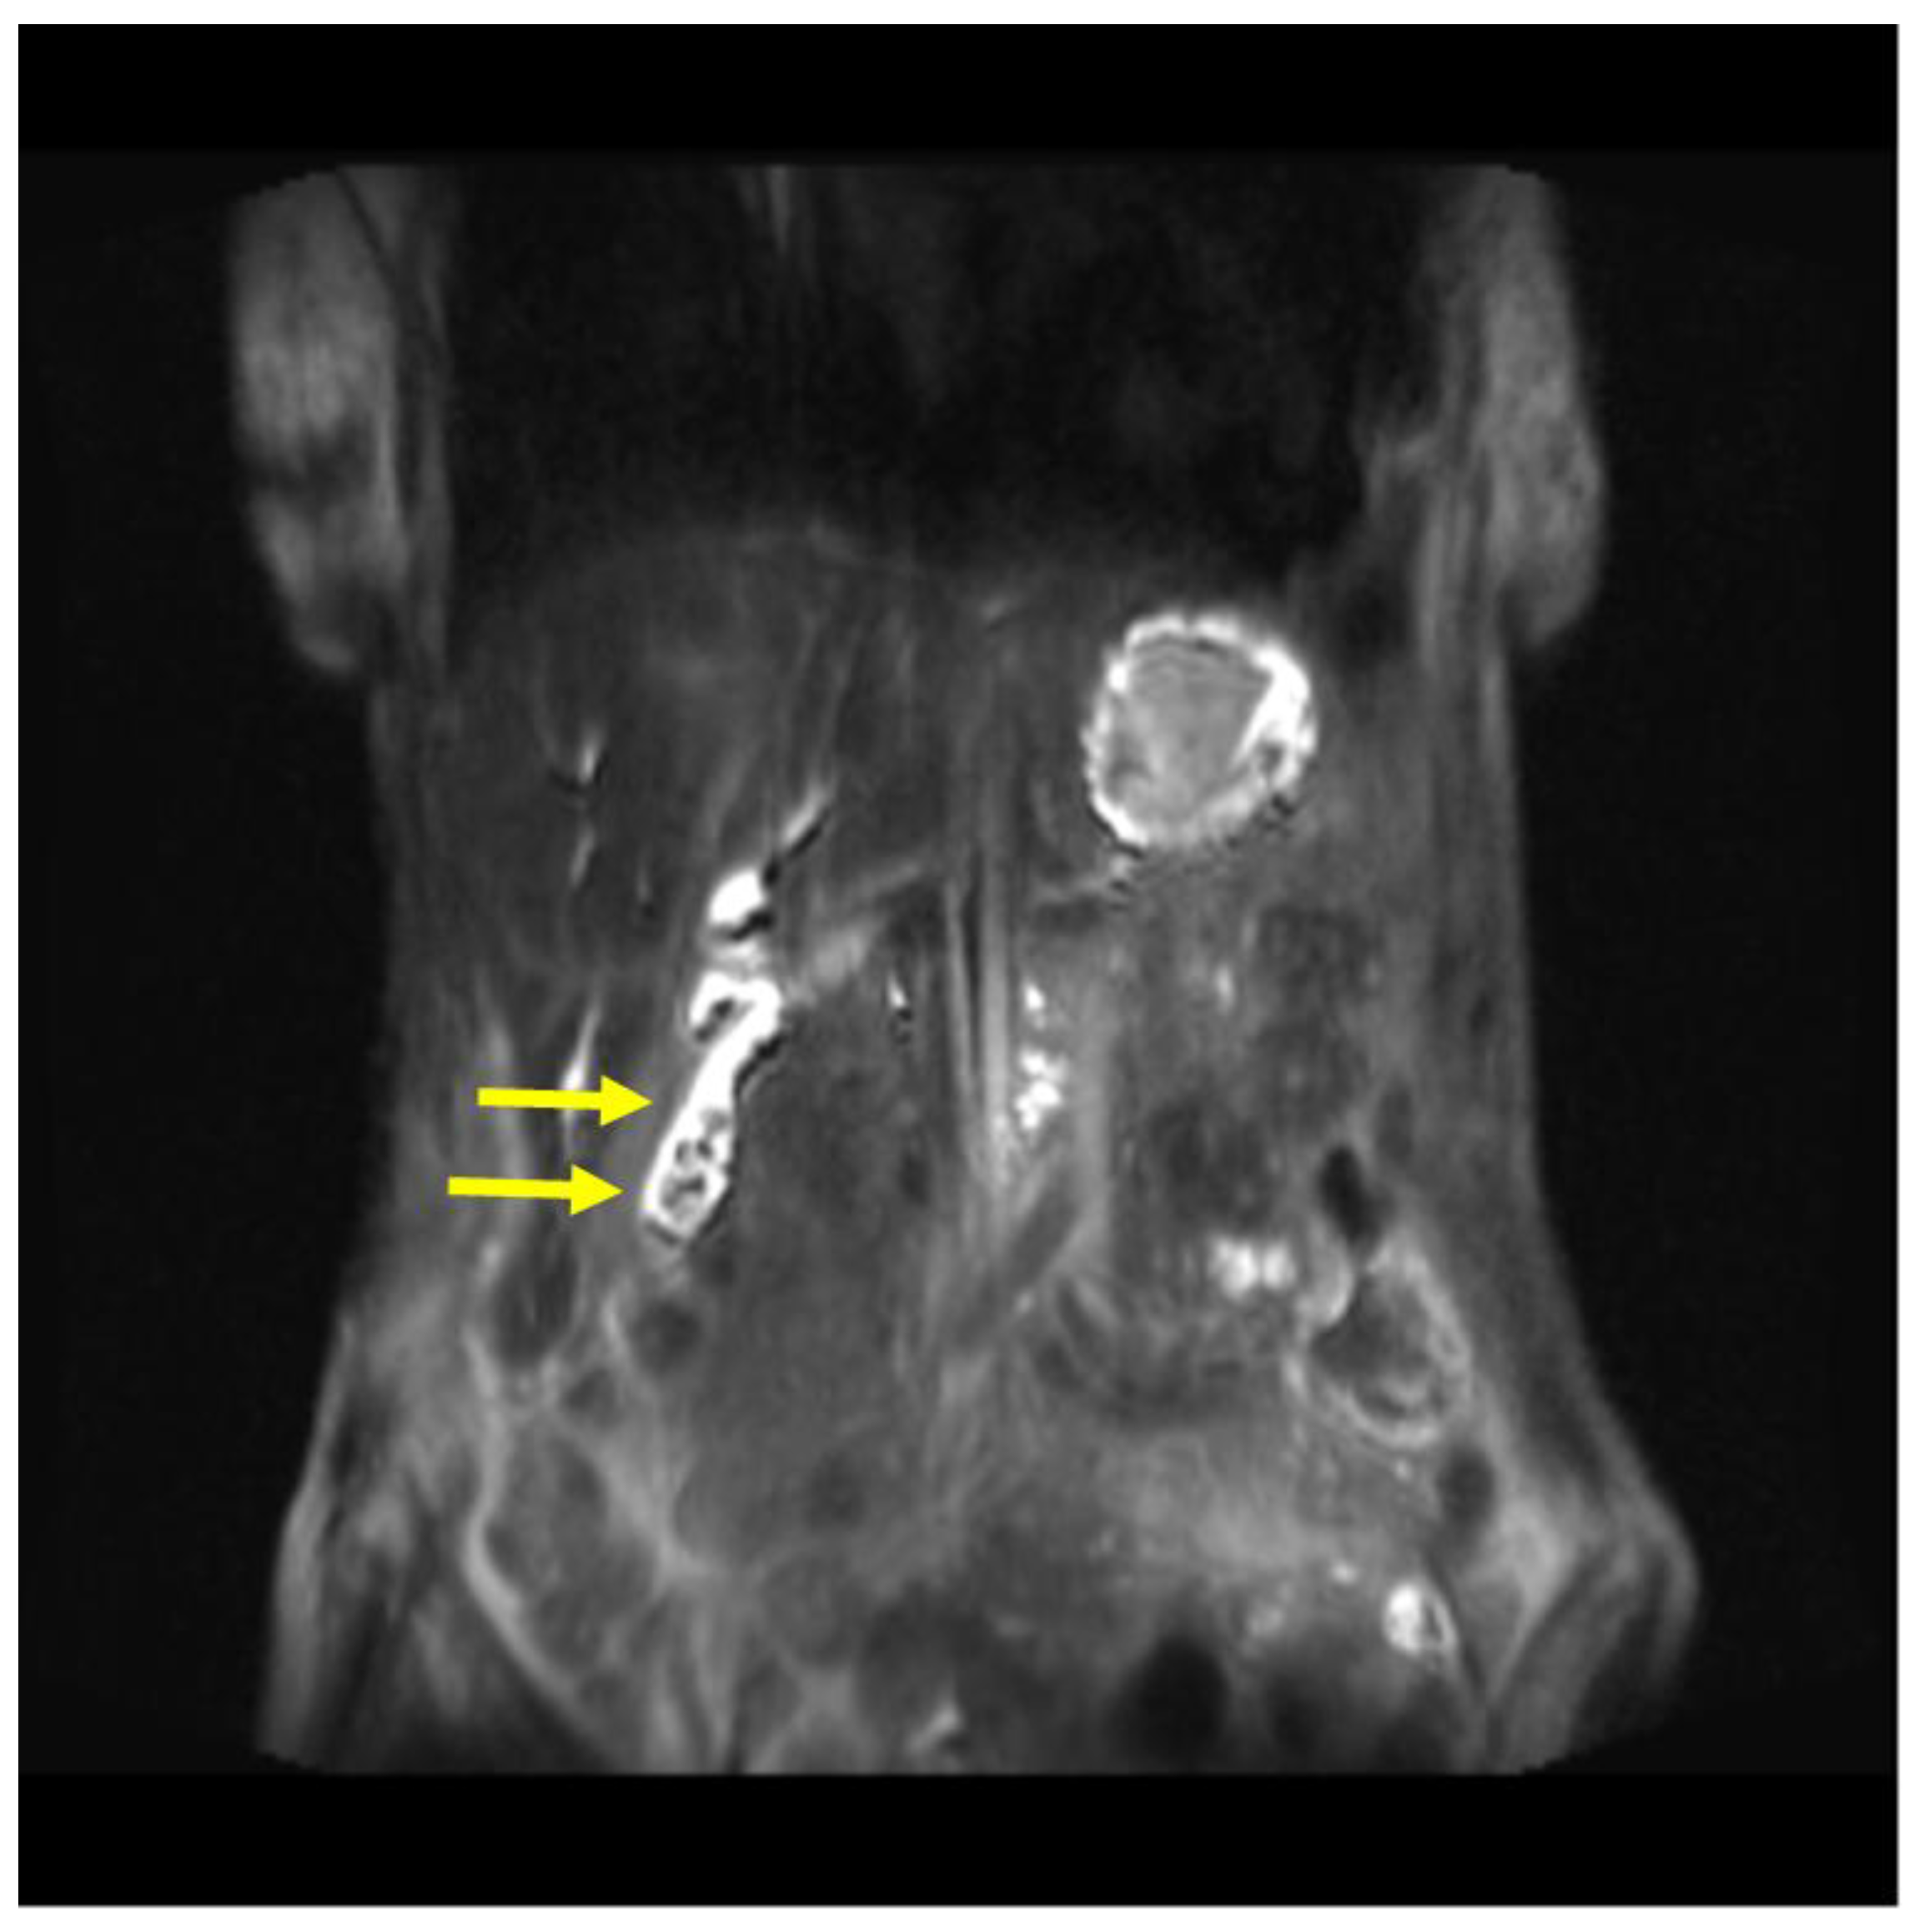

Magnetic resonance cholangiopancreatography (MRCP) on postoperative day 17 demonstrated the presence of a remnant gallbladder (GB) containing multiple calculi (Figure 4, Figure 5). In conclusion, debridement resulted in an inadvertent subtotal cholecystectomy. The patient was discharged on postoperative day 21 with a recommendation for completion cholecystectomy. She neglected this indication and, once again, was lost for follow-up for more than one year.

Figure 4. MRCP (coronal, HASTE T2 sequence demonstrating multiple remnant gallbladder (GB) calculi (yellow arrows).